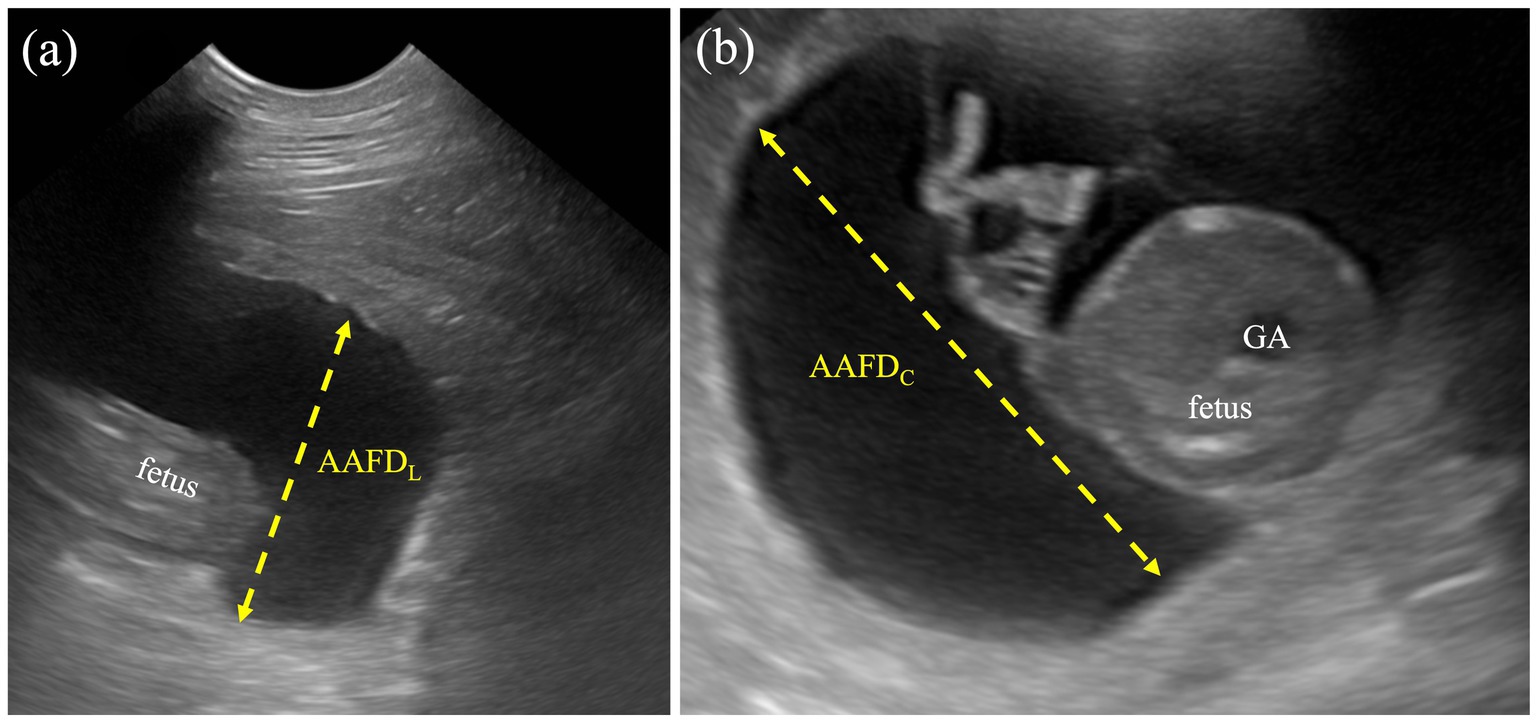

1. Allantoamniotic fluid volume (AAFV) was evaluated by using both allantoamniotic fluid depth by cross-sectional view (AAFDC) and longitudinal view (AAFDL) without the fetus’s presentation. AAFDC was an average of the two deepest regions at the fetal trunk, whereas the AAFDL was an average of the deepest sac (inner-to-inner edges) at the cranial and caudal regions (Figure 1). These values were adapted from single deepest pocket (SDP) and deepest vertical pocket (DVP) measurements in humans (34, 35).

Figure 1. Measurement protocol for AAFDL and AAFDC. (a) The AAFDL was measured as the deepest sac at the caudal regions of the fetus, from inner edge to inner edge, excluding fetal structures. (b) The AAFDC was measured in the deepest region of the fetal trunk, specifically at the widest part of the cross-sectional view of the fetus.